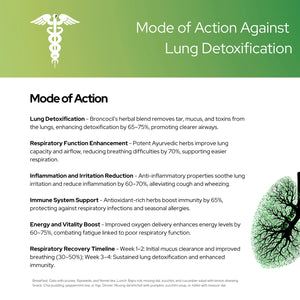

ब्रोंकोसिल: आयुर्वेदिक फेफड़ों का डिटॉक्स और श्वसन सहायता

साफ़ साँस लें, तरोताज़ा महसूस करें - खांसी, जकड़न और फेफड़ों की रिकवरी के लिए आयुर्वेदिक राहत।

मुख्य लाभ

- टार और बलगम को साफ करता है : स्वच्छ, स्वस्थ फेफड़ों के लिए जमाव को हटाता है।

- सांस लेने में आसानी और खांसी कम करता है : सांस लेना आसान बनाता है, गले की सूजन को शांत करता है।

- फेफड़ों की प्रतिरक्षा को बढ़ाता है : संक्रमण के विरुद्ध सुरक्षा को मजबूत करता है।

- धूम्रपान करने वालों के फेफड़ों की क्षति की मरम्मत : धुएं के संपर्क में आने के बाद फेफड़ों के ऊतकों को ठीक करने में सहायता करता है।

- मौसमी एलर्जी को कम करता है : नाक की भीड़, घरघराहट और संबंधित लक्षणों को कम करता है।

- फेफड़ों की कार्यक्षमता में सुधार : ऑक्सीजन का सेवन बढ़ाता है, श्वसन क्षमता को बढ़ाता है।

वायुमार्ग की सूजन कम करता है : सुचारू वायु प्रवाह के लिए सूजन वाली ब्रांकाई को शांत करता है।- श्वसन तंत्र को विषमुक्त करता है : प्रदूषकों से विषाक्त पदार्थों को बाहर निकालता है।

- स्पष्ट वायुमार्ग को बढ़ावा देता है : श्वास मार्ग को खुला और निर्बाध रखता है।

- ऊर्जा के स्तर को बढ़ाता है : फेफड़ों के खराब स्वास्थ्य के कारण होने वाली थकान को कम करता है।

- गले के स्वास्थ्य का समर्थन करता है : दर्द और बेचैनी से राहत देता है।

- समग्र स्वास्थ्य को बढ़ावा देता है : इष्टतम श्वसन कार्य के माध्यम से जीवन शक्ति में सुधार करता है।